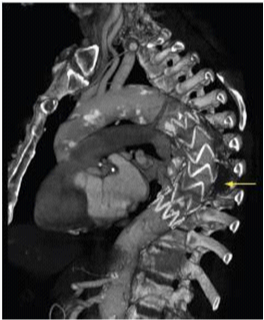

TEVAR is a less invasive technique compared to conventional surgery and its availability and relative ease of application, amplified and changed the options in the management of thoracic aortic disease, including patients considered unfit for conventional surgery (Figure 3).10

Figure 3 CT Angiography after TEVAR.10